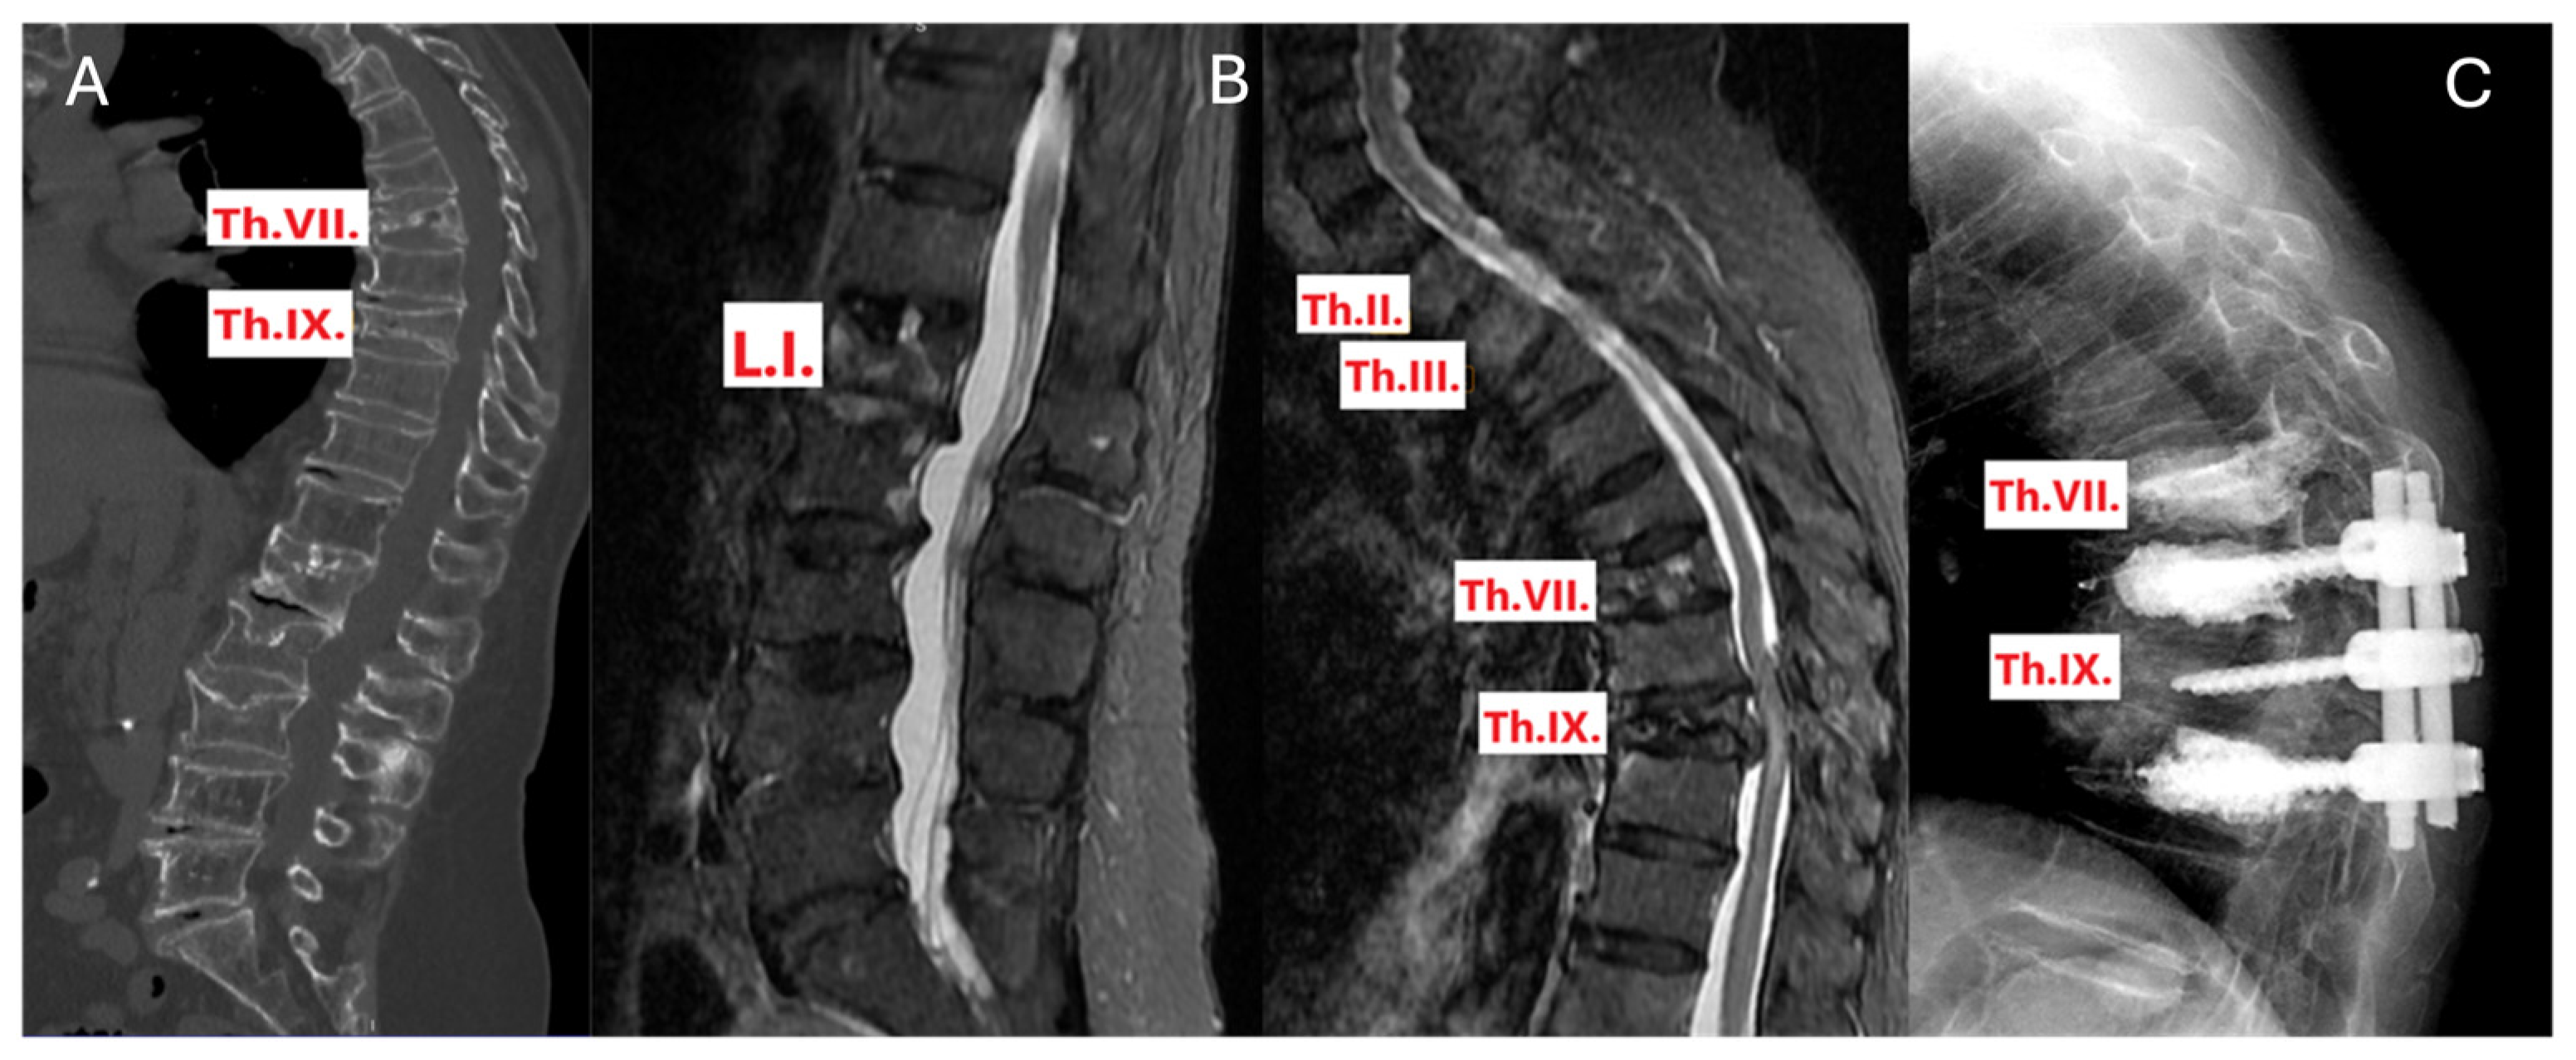

3.5.2. Case 2: Surgical Treatment Modification